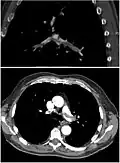

CT pulmonary angiography

CT pulmonary angiography (CTPA) is a pulmonary angiogram obtained using computed tomography (CT) with radiocontrast rather than right heart catheterization. Its advantages are that it is accurate, it is non-invasive, it is more often available, and it may identify other lung disorders in case there is no pulmonary embolism. The accuracy and non-invasive nature of CTPA also make it advantageous for people who are pregnant.[61]

Assessing the accuracy of CT pulmonary angiography is hindered by the rapid changes in the number of rows of detectors available in multidetector CT (MDCT) machines.[62] According to a cohort study, single-slice spiral CT may help diagnose detection among people with suspected pulmonary embolism.[63] In this study, the sensitivity was 69% and specificity was 84%. In this study which had a prevalence of detection was 32%, the positive predictive value of 67.0% and negative predictive value of 85.2%. However, this study's results may be biased due to possible incorporation bias, since the CT scan was the final diagnostic tool in people with pulmonary embolism. The authors noted that a negative single-slice CT scan is insufficient to rule out pulmonary embolism on its own. A separate study with a mixture of 4-slice and 16-slice scanners reported a sensitivity of 83% and a specificity of 96%, which means that it is a good test for ruling out a pulmonary embolism if it is not seen on imaging and that it is very good at confirming a pulmonary embolism is present if it is seen. This study noted that additional testing is necessary when the clinical probability is inconsistent with the imaging results.[64] CTPA is non-inferior to VQ scanning, and identifies more emboli (without necessarily improving the outcome) compared to VQ scanning.[65]